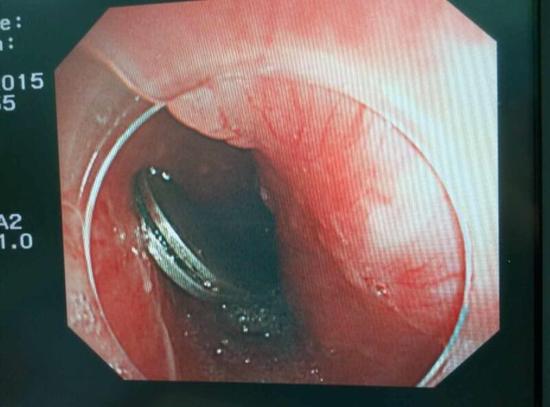

醫(yī)生從華先生胃里取出的鑷子和打火機

手術(shù)中,范醫(yī)生通過胃鏡準(zhǔn)確發(fā)現(xiàn)了胃里的鑷子。但讓他驚訝的是,在華先生胃底竟然還躺著三個被腐蝕了的打火機,打火機的金屬部件都已經(jīng)不見了。

隨后,范醫(yī)生先用圈套器套取出了長10厘米的鑷子,再一個一個地取出了打火機。整個取出過程小心謹(jǐn)慎而又一氣呵成,只用了不到10分鐘。